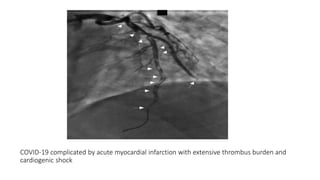

COVID‐19 complicated by acute myocardial infarction with extensive thrombus burden

and cardiogenic shock

Catheterization and Cardiovascular Interventions, First published: 19 May 2020, DOI: (10.1002/ccd.28992)